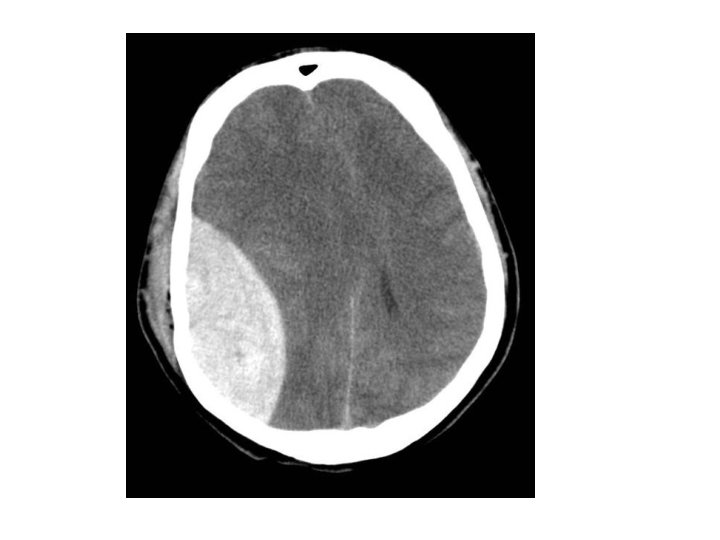

Acute Subdural haematoma • • • Crescentic hyperdense lesion Effacement of the lateral ventricle Midline shift Damage to bridging veins T

Extradural Haematoma • • • Biconvex(lens shaped) hyperdense lesion Effacement of ipsilateral ventricle Midline shift Lucid interval is a common feature Emergency craniotomy